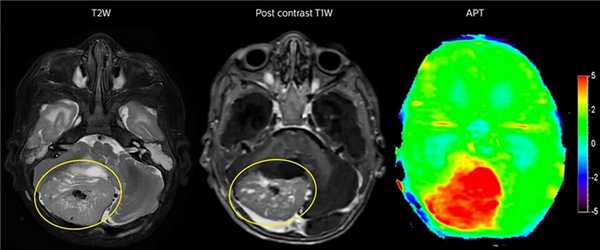

Проведение МРТ головного мозга с контрастом

Контрастное исследование предпочтительно при подозрении на опухоли или уже установленном диагнозе, если больного проверяли раньше другими методами. Контраст, введенный в кровь, попадает в мозг и делает более заметными патологические очаги на фоне здоровых тканей. По скорости и характеру накопления контрастного вещества, границам очага врач может отличить доброкачественную опухоль от злокачественной.

Без внутривенного контрастирования С внутривенным контрастированием